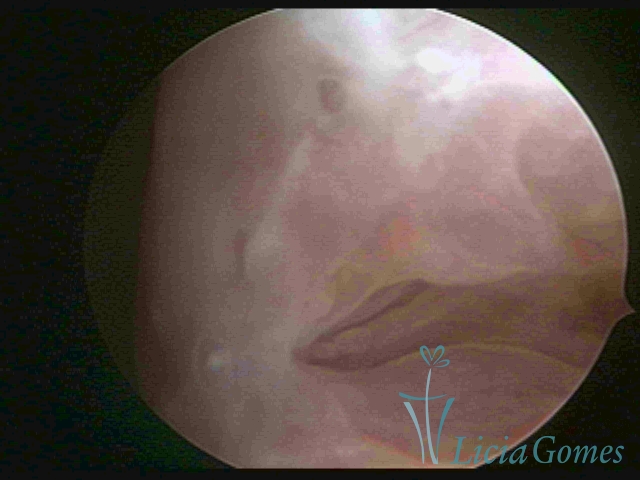

Second part or middle section

In the middle section of the cervical canal, the details of the buds are lost. It is possible to view creases and crypts. Longitudinal grooves are frequently observed. They are the most compact tissues presenting the most vascularized surface, whose vessels follow its passageway.